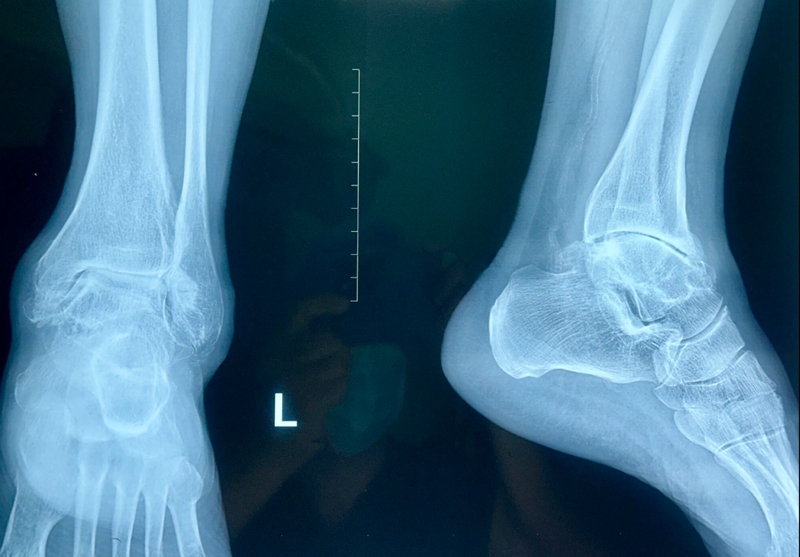

病例报告之二,xx,男,56岁,左踝创伤性关节炎。左踝崴伤6年,疼痛加剧3年。切口显露同前。

手术前资料